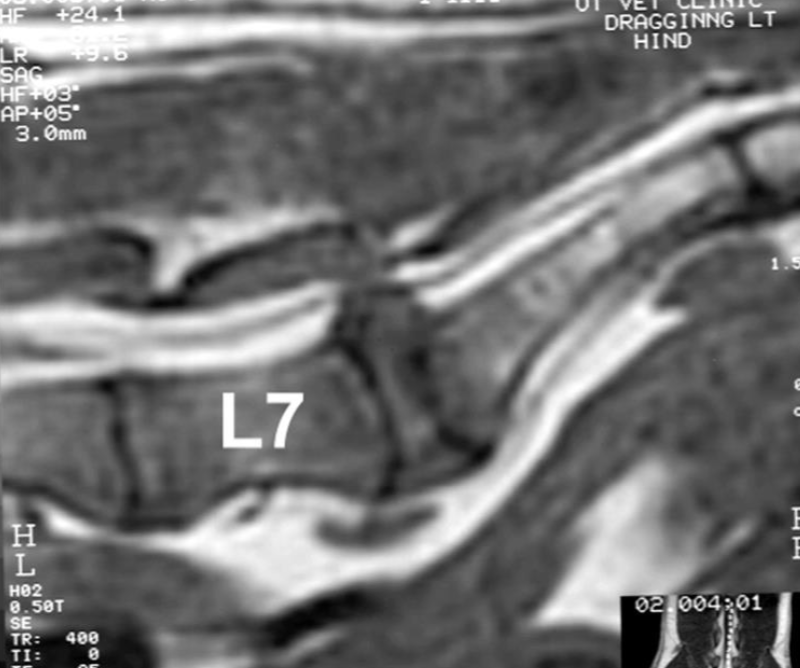

What is shown in this image?

A

MRI identifying disc protrusion/displacement of spinal cord